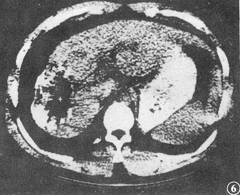

图3 TAE术前CT片,肝右叶病灶5.9cm×4.8cm

图4 同上例手术切除标本,整个病灶呈凝固性坏死,与非癌肝组织间有纤维组织形成的包膜